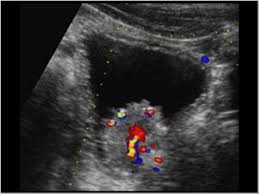

Color Doppler Ultrasound Bladder Cancer Youtube

Color Doppler Ultrasound Bladder Cancer Youtube from i.ytimg.com